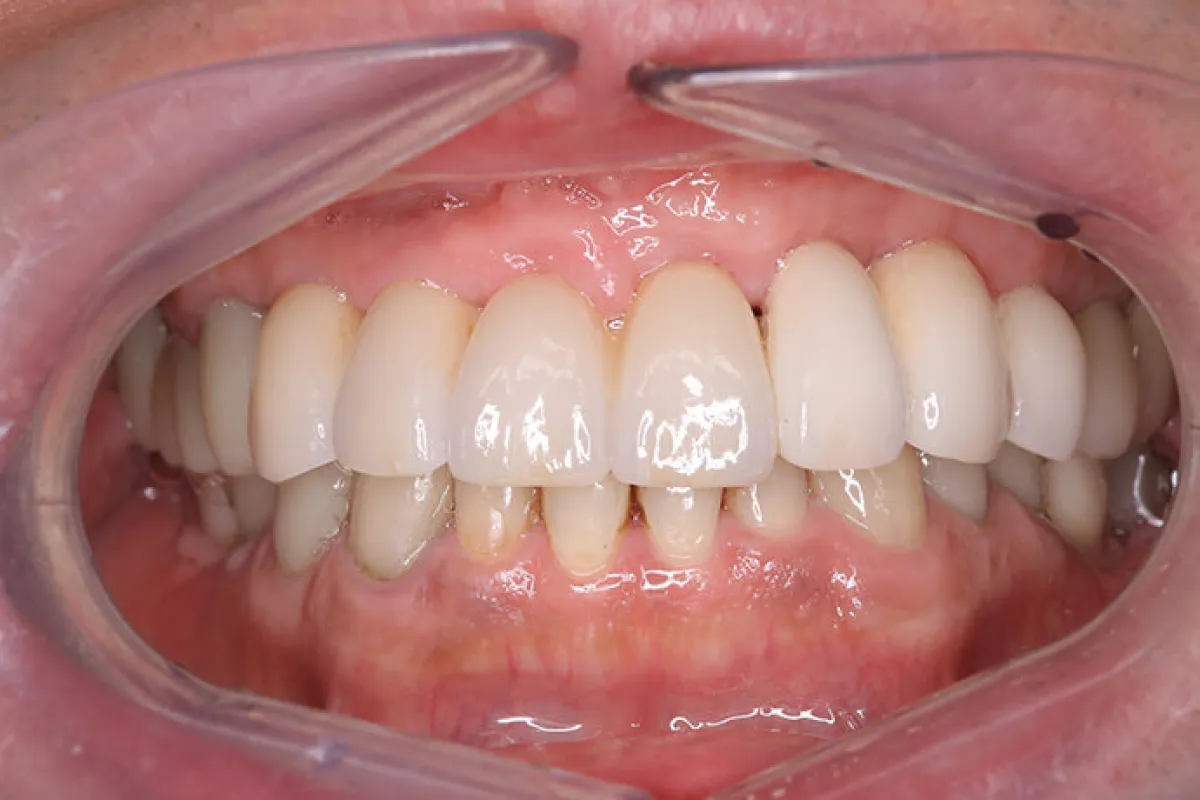

患者様情報 60代女性 患者様のお悩み 被せものがはずれた、前歯のブリッジがぐらぐらする 治療概要 虫歯治療、詰め物・被せ物、インプラント 提案内容 奥歯は金属修復補綴物の劣化、隙間からの虫歯があったので治 […]